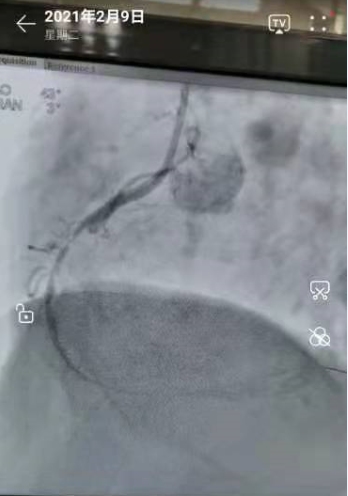

2021年2月9日,心血管内三科的医生们,在导管室正常做着介入手术!今天共3个患者。最后一台是一个胸痛的病人,造影:右冠闭塞99%。与家属沟通后,我们积极地做了开通血管的介入手术。

导丝通过顺利——球囊扩张到位——安放支架成功!

手术完美!